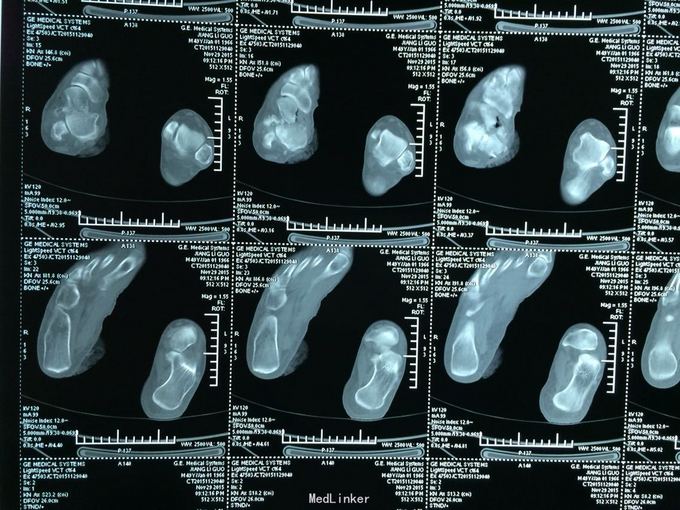

距骨开放性粉碎性骨折

骨折 胫距关节脱位 距骨开放性粉碎性骨折

外伤后右踝肿痛、畸形、出血1小时 1小时前搬重物时扭伤右踝,内踝处有一8厘米长横形伤口,内踝骨质外露,胫后动脉神经外露

见上图

右距骨开放性粉碎性骨折并胫距关节脱位 入院后急诊行伤口清创缝合并跟骨牵引术